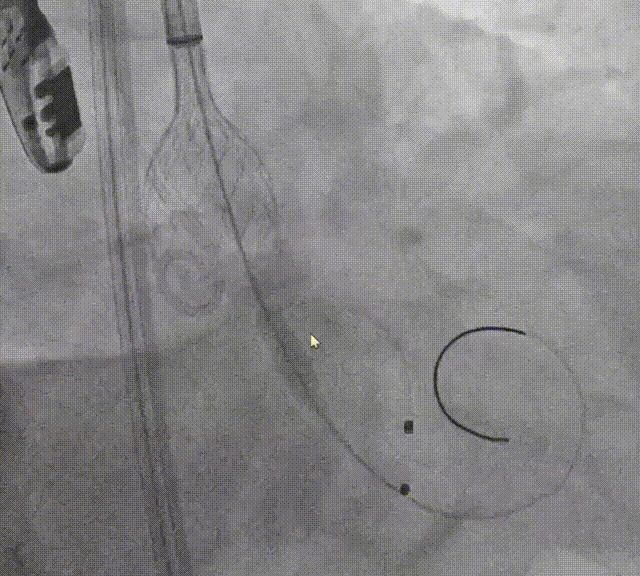

球囊预扩张

10mm*10cm小球囊预扩

23mm Z-Med预扩张

根据预扩表现决定使用26mm瓣膜